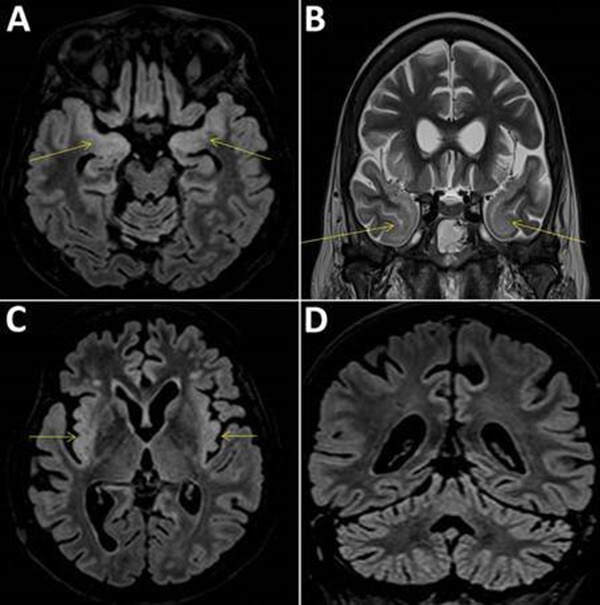

Một phụ nữ giấu tên 58 tuổi ở Paris, Pháp vừa qua đời vì viêm não. Các nhà khoa học đã tiến hành xét nghiệm coronavirus và vô tình tìm thấy một loại virus mới có thể lây truyền qua đường muỗi đốt và đặt tên là virus Cristoli.

Các nhà khoa học nói rằng virus Cristoli thuộc chi Orthobunyavirus và thường lây lan do muỗi đốt.